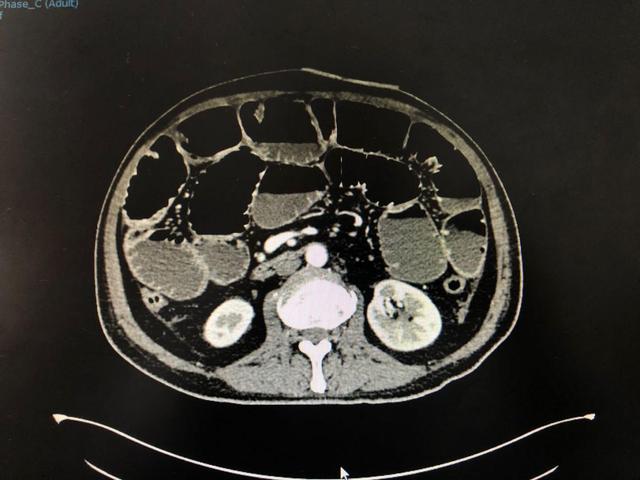

入院时,李大爷已有明显的腹痛、腹胀,伴有胸闷、心悸,恶心、呕吐等症状。胸腹部 CT 检查诊断局限性肺不张、感染及胸腔积液。小肠明显扩张并见数个气液平面,伴有腹腔积液。

孙士东主任医师带领消化科团队经过仔细的病情分析和充分的风险评估,决定对其实施「胃镜下经鼻肠梗阻导管置入术」。手术过程顺利,无任何不良反应。术后予以加强营养支持、促动力药、低频脉冲治疗,24 小时导管下行约 170 cm,引流肠内容物约 2000 ml。